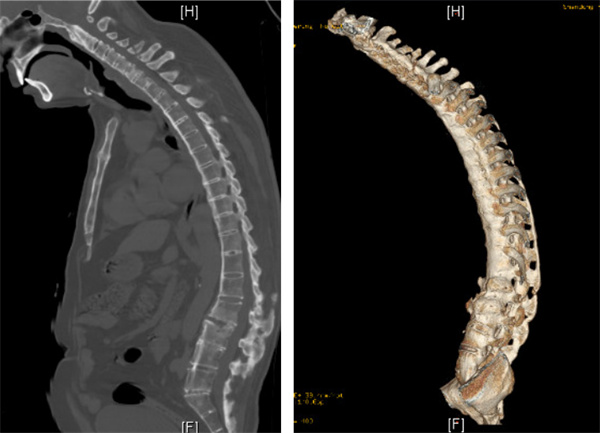

省立首例C7经椎弓根闭合式楔形截骨(PSO)技术

颈胸段后凸畸形,“颌触胸”,不能平视。PSO可矫正25-30度,对颈胸段后凸畸形矫正具有精准截骨、脊柱序列重建效果佳的特点,术中通过闭合式操作减少软组织剥离与出血,降低椎管内神经损伤风险,术后脊柱稳定性恢复快,为高难度脊柱畸形矫正积累了宝贵的临床经验,填补了省内该技术领域的应用空白。